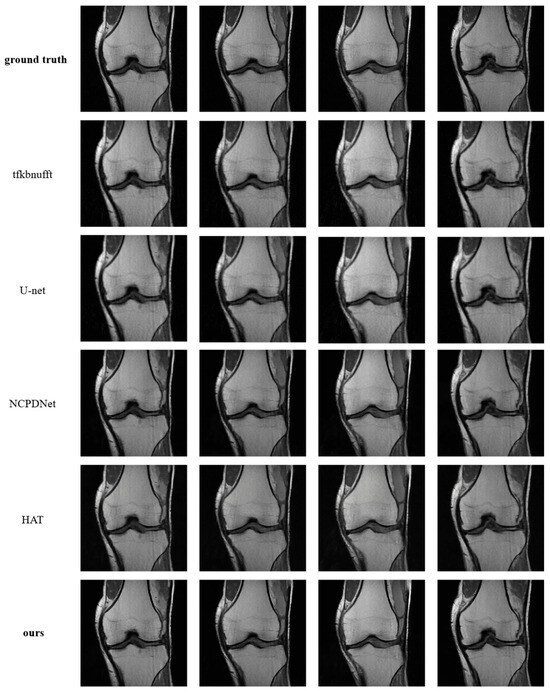

Super-Resolution Reconstruction Approach for MRI Images Based on Transformer Network

by Xin Liu, Chuangxin Huang, Jianli Meng, Qi Chen, Wuzheng Ji and Qiuliang Wang

AI 2025, 6(11), 291; https://doi.org/10.3390/ai6110291 - 14 Nov 2025

Magnetic Resonance Imaging (MRI) serves as a pivotal medical diagnostic technique widely deployed in clinical practice, yet high-resolution reconstruction frequently introduces motion artifacts and degrades signal-to-noise ratios. To enhance imaging efficiency and improve reconstruction quality, this study proposes a Transformer network-based super-resolution framework [...] Read more.

Magnetic Resonance Imaging (MRI) serves as a pivotal medical diagnostic technique widely deployed in clinical practice, yet high-resolution reconstruction frequently introduces motion artifacts and degrades signal-to-noise ratios. To enhance imaging efficiency and improve reconstruction quality, this study proposes a Transformer network-based super-resolution framework for MRI images. The methodology integrates Nonuniform Fast Fourier Transform (NUFFT) with a hybrid-attention Transformer network to achieve high-fidelity reconstruction. The embedded NUFFT module adaptively applies density compensation to k-space data based on sampling trajectories, while the Mixed Attention Block (MAB) activates broader pixel engagement to amplify feature extraction capabilities. The Interactive Attention Block (IAB) facilitates cross-window information fusion via overlapping windows, effectively suppressing artifacts. Evaluated on the fastMRI dataset under 4× radial undersampling, the network demonstrates 3.52 dB higher PSNR and 0.21 SSIM improvement over baselines, outperforming state-of-the-art methods across quantitative metrics. Visual assessments further confirm superior detail preservation and artifact suppression. This work establishes an effective pipeline for high-quality radial MRI reconstruction, providing a novel technical pathway for low-field MRI systems with significant research and application value. Full article